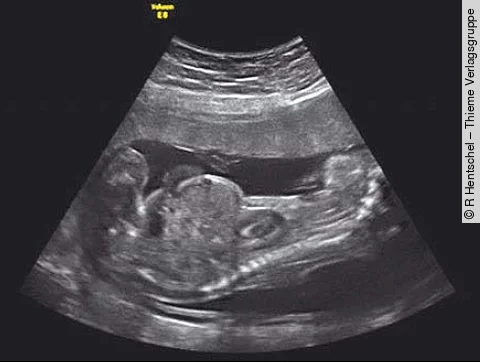

Eine 38-jährige Frau ist nach spontaner Empfängnis schwanger mit monochorioten, diamnioten Zwillingen. Ihre Krankengeschichte umfasst eine Wirbelsäulenentzündung und Tagesschläfrigkeit.